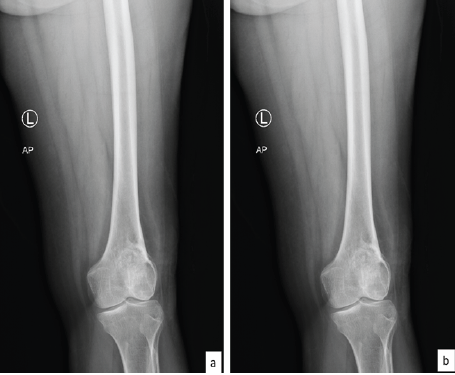

The patient is a 44-year-old female who presented with a progressively enlarging, painful swelling in the left distal femur. The swelling had been present for several months and was associated with localized pain that worsened over time. Radiographic imaging (Fig. 1) revealed an osteolytic lesion in the distal femur with ill-defined margins and a narrow zone of transition, suggestive of a GCT (Campanacci grade 2). Magnetic resonance imaging (MRI) of the lesion (Fig. 2) was done which revealed a well-defined lesion in epi-metaphyseal lesion measuring 64 × 52 × 38 mm on the left side of distal femur, associated with a large soft tissue mass, with no intra-articular extension.

Figure 1: Pre-operative X-rays showing lesion in left distal femur; (a) anteroposterior and (b) lateral view.